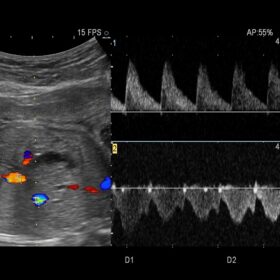

Ultrasound ARIETTA V60 – Image Gallery and Videos

Radiology 2D, Color, Contrast and Elasto mode

- Blood flow information can be easily acquired. The sharply delineated Doppler waveform is easy to measure.